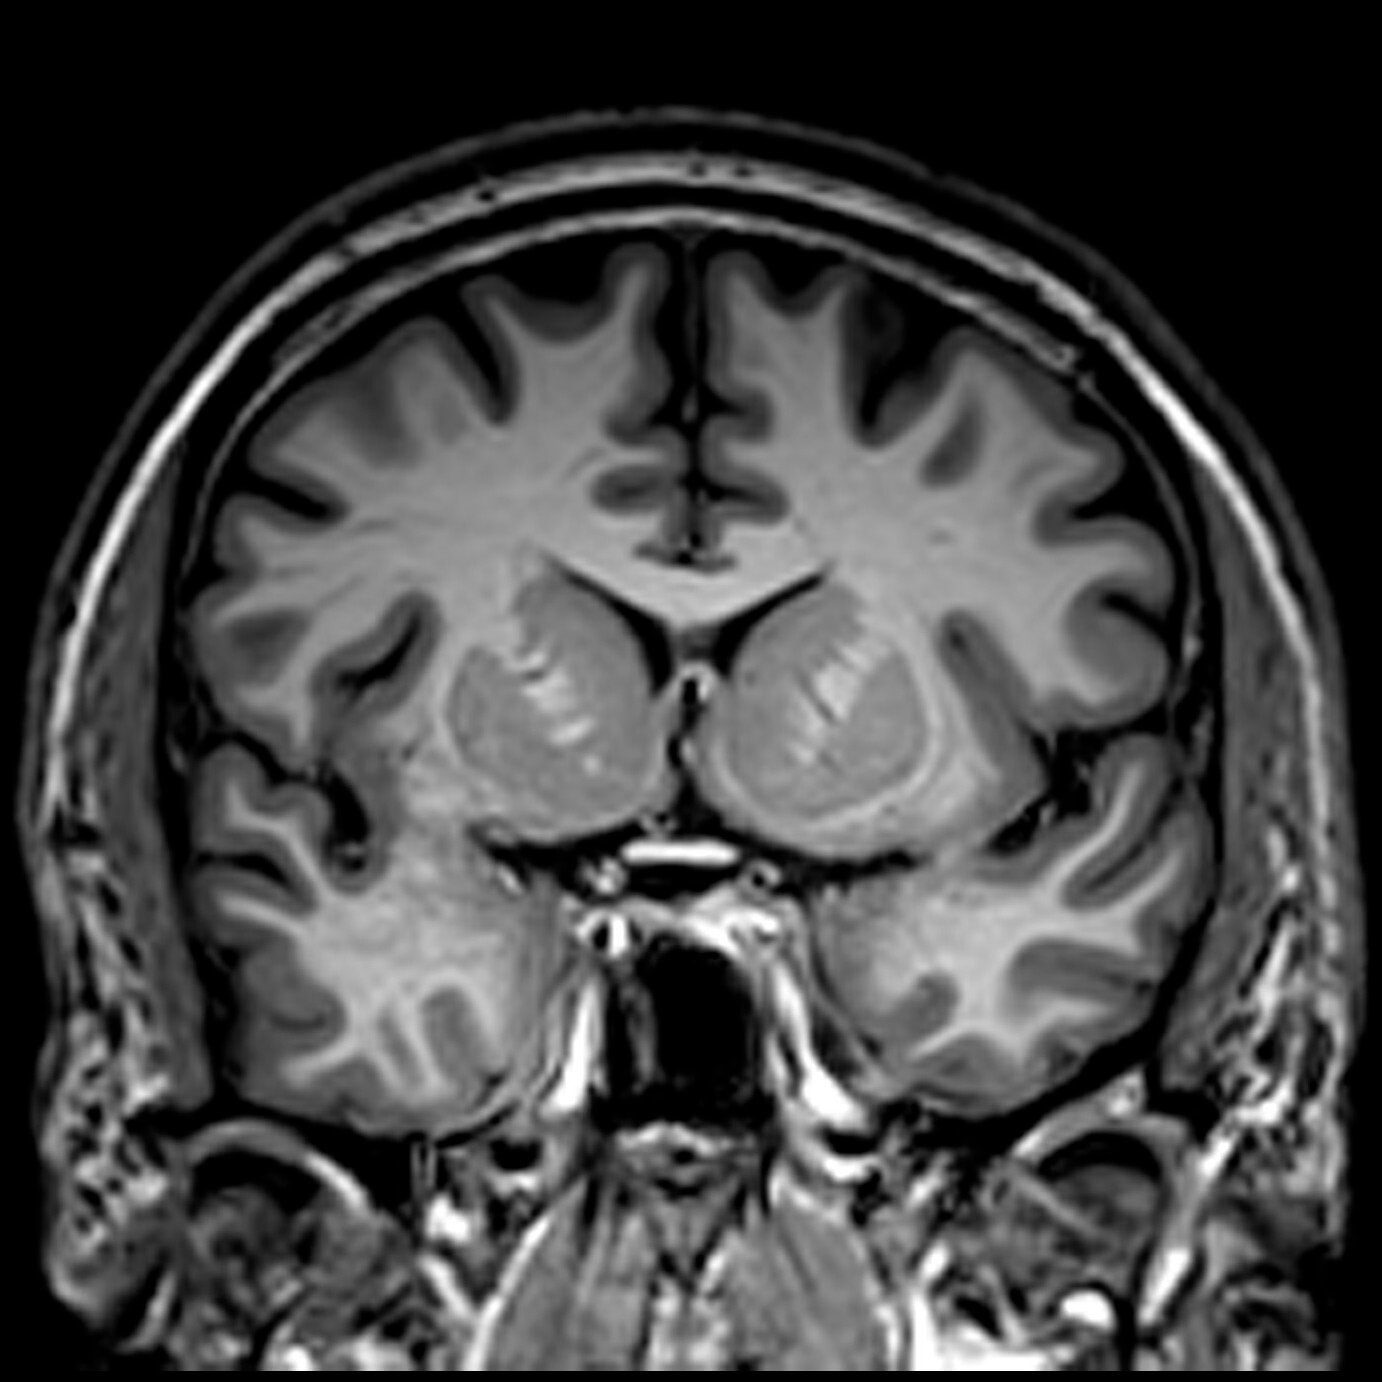

Neuro